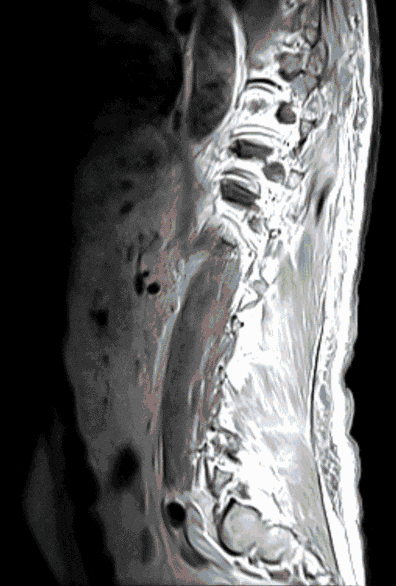

Metastases

In approximately 5% of all cancer patients (e.g. patients with lung, prostate or breast cancer), the spine is affected by metastases. Metastases can endanger the stability of the spine or lead to pain and neurological dysfunction due to pressure on the spinal cord and nerves.